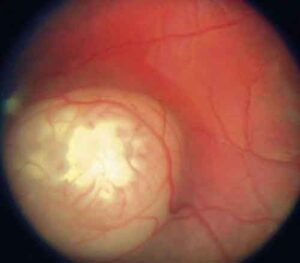

Sta dando risultati positivi il protocollo messo in atto dall'azienda ospedaliera delle Scotte di Siena per la cura del retinoblastoma,...

Raro ma aggressivo, questo tumore colpisce soprattutto i bambini Si guarisce quasi sempre e ora si punta a preservare la...